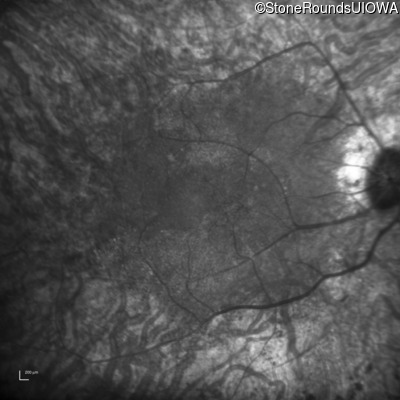

Infrared Fundus Photograph - Right - 20/40 +1

Exemplar